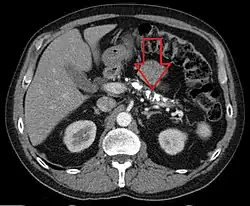

![]() Axial CT showing multiple calcifications in the pancreas in a patient with chronic pancreatitis Axial CT showing multiple calcifications in the pancreas in a patient with chronic pancreatitis | |

يعتمد تشخيص التهاب البنكرياس المزمن عادةً على الاختبارات التي تجرى على بنية البنكرياس ووظائفه، حيث تعتبر الخزعة المباشرة للبنكرياس شديدة الخطورة. إن أنزيما الأميلاز والليباز في مصل الدم قد يرتفعا أو لا يرتفعا بصورة معتدلة في حالات التهاب البنكرياس المزمن بسبب تذبذب مستويات تلف الخلايا المنتجة، ومع ذلك يكون ارتفاع مستوى أنزيم الليباز هو الأرجح حدوثًا بين الأنزيمين. وترتفع مستويات الأميلاز والليباز دائمًا تقريبًا في الحالات الحادة مع ارتفاع مستوى البروتين المتفاعل-C (CRP) المسبب للالتهاب والذي يتماشى بدرجة كبيرة مع شدة الحالة. ويعتبر اختبار تحفيز السيكريتين الاختبار الوظيفي ذي المعيار الذهبي لتشخيص التهاب البنكرياس المزمن، إلا أنه لا يُستخدم كثيرًا إكلينيكيًا. ويُذكر أن ملاحظة أنه تتم إعاقة إنتاج البيكربونات في مرحلة مبكرة من التهاب البنكرياس المزمن أدت إلى التوصل إلى الأساس المنطقي لاستخدام هذا الاختبار في المراحل المبكرة من المرض (بدرجة حساسية تبلغ 95%). ومن بين الاختبارات الأخرى الشائعة التي تُستخدم لتحديد حالة التهاب البنكرياس المزمن قياس نسبة أنزيم الإيلاستاز الغائطي في البراز والتريبسونجين في مصل الدم والتصوير المقطعي المحوسب (CT) والموجات فوق الصوتية والتنظير الباطني بالموجات فوق الصوتية (EUS) والتصوير بالرنين المغناطيسي (MRI) وتصوير البنكرياس بالتنظير الباطني بالطريق الراجع (ERCP) وتصوير البنكرياس بالرنين المغناطيسي (MRCP). وفي الغالب، يمكن رؤية التكلس البنكرياسي من خلال الأشعة السينية العادية على البطن فضلاً عن التصوير المقطعي المحوسب (CT).